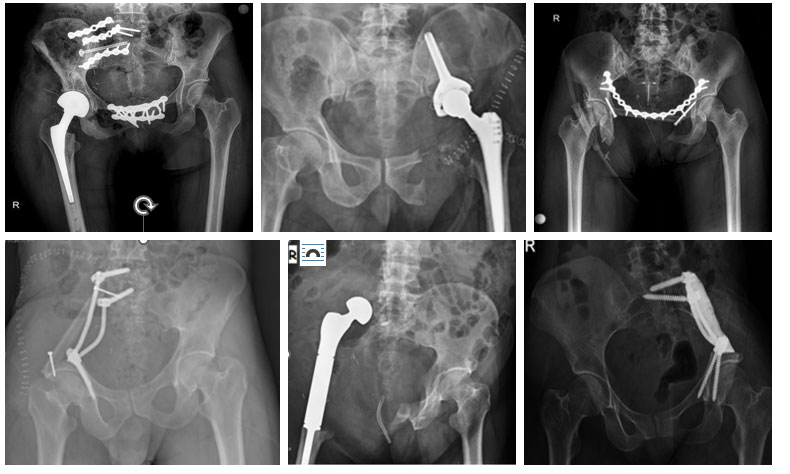

All types of cancer can metastasize to the pelvis and acetabulum region, and they metastasize to this region most frequently after the spine. The surgical treatment for many bone metastases located in the pelvis and acetabulum involves filling the void formed after cleaning the tumor (curettage) with bone cement and, in patients who require it, treating it by strengthening with fixation (plate and screw). In cases where this method is thought to be unsuccessful or insufficient, we perform resection (hemipelvectomy) and, in suitable patients, reconstruction (restructuring).

The surgical treatment of bone sarcomas (Osteosarcoma, Ewing sarcoma, and Chondrosarcoma) located in the pelvis and acetabulum is the removal (resection) of the tumor with clean, that is, wide margins. Due to the anatomical location, this surgical procedure is called hemipelvectomy. Hemipelvectomy is the highest level and most complex surgery of orthopedic oncology, requiring serious experience and meticulous planning.

Hemipelvectomy is mainly of two types: internal and external. In internal hemipelvectomy, the leg on the same side is preserved, whereas in external hemipelvectomy, the tumor is removed together with the leg.

We frequently perform internal hemipelvectomy in sarcoma cases located in the pelvis and acetabulum. However, external hemipelvectomy may be applied in recurrent cases, in cases where 2 of the 3 main structures (hip joint, sciatic and femoral nerves) cannot be preserved, in situations where major vessels (external iliac and femoral arteries) cannot be preserved and reconstructed, where soft tissue coverage cannot be provided, and in the presence of uncontrollable infection.

Internal hemipelvectomy is usually the removal of one entire half of the tumorous pelvic bone or a region of it, and it is typed according to the removed region. There are mainly 4 types.

Type 1: Iliac wing resection. It is a relatively easier and lower-risk resection. The formed void is often reconstructed with rods and screws and/or fibula, bone cement, recycling, and fixation. Leaving it empty after reconstruction is also an option, though we very rarely apply this method.

Type 2: Acetabulum, that is, hip joint resection. It is a relatively more complex resection type that can leave a disability. The risk of injury to the main vessels (external iliac artery and vein) and nerves (sciatic and femoral) is higher. The void formed after resection is frequently reconstructed with a prosthesis (ice-cream, LUMiC, etc.). A hip prosthesis combined with recycling is another option. Depending on the size of the tumor, resection combined with Type 1 and/or 3 can be applied.

Type 3: Resection of the pubic rami. It is a specialized surgery due to the proximity of internal organs (bladder, urethra, etc.) and major vessels (femoral artery, vein), and due to muscles (hamstring, adductor, etc.) and ligaments (sacrotuberous). The void formed after surgery is often closed with a prolene mesh to prevent hernia development. In bilateral resections, reconstruction with fibula and plate can be applied.

Type 4: Named when the sacrum is included. It is often performed together with Type 1 resection and is called sacroiliac resection. If the resection margin has to be applied closer to the inner side, injury to the nerves we call sacral roots and, although rare, consequent adverse effects on urinary, fecal, and sexual functions may develop.

In some cases, we have to combine these resections. For example, Type I+II, I+IV, Type II+III.

Reconstruction (restructuring) of the void formed after internal hemipelvectomy can be done with many different methods. Although the most frequently performed reconstruction methods are tumor prosthesis (hip transposition, ice-cream/LUMiC prosthesis, etc.), fibula, and/or recycling (liquid nitrogen or radiotherapy), leaving it empty without reconstruction can also be applied as an option. The type of resection applied, the remaining bone stock, and the general condition of the patient are particularly important in deciding on the reconstruction to be performed.